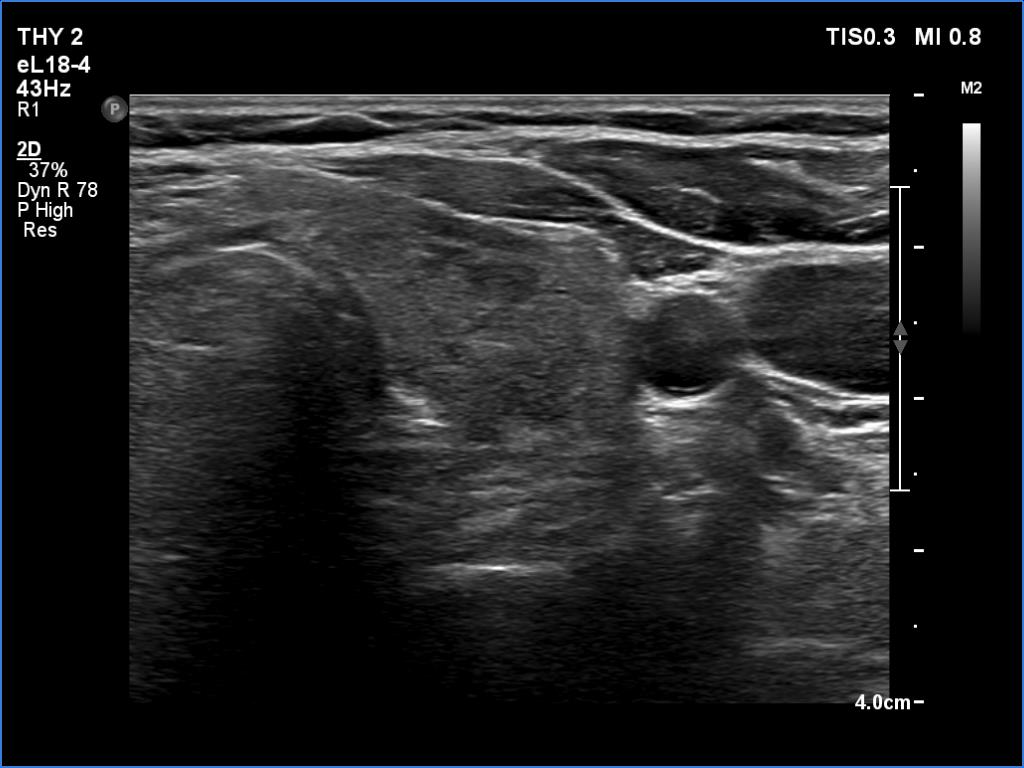

Palpation: The right lobe was suspicious having a nodule.

Ultrasonography. The thyroid was minimally hypoechoic and had several discrete areas of various echogenicities. None of these lesions corresponded to true nodule.